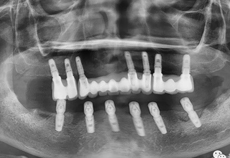

治疗前CT照

治疗过程:导板引导下下颌外科手术植入6颗种植体

治疗过程:植入6颗种植体